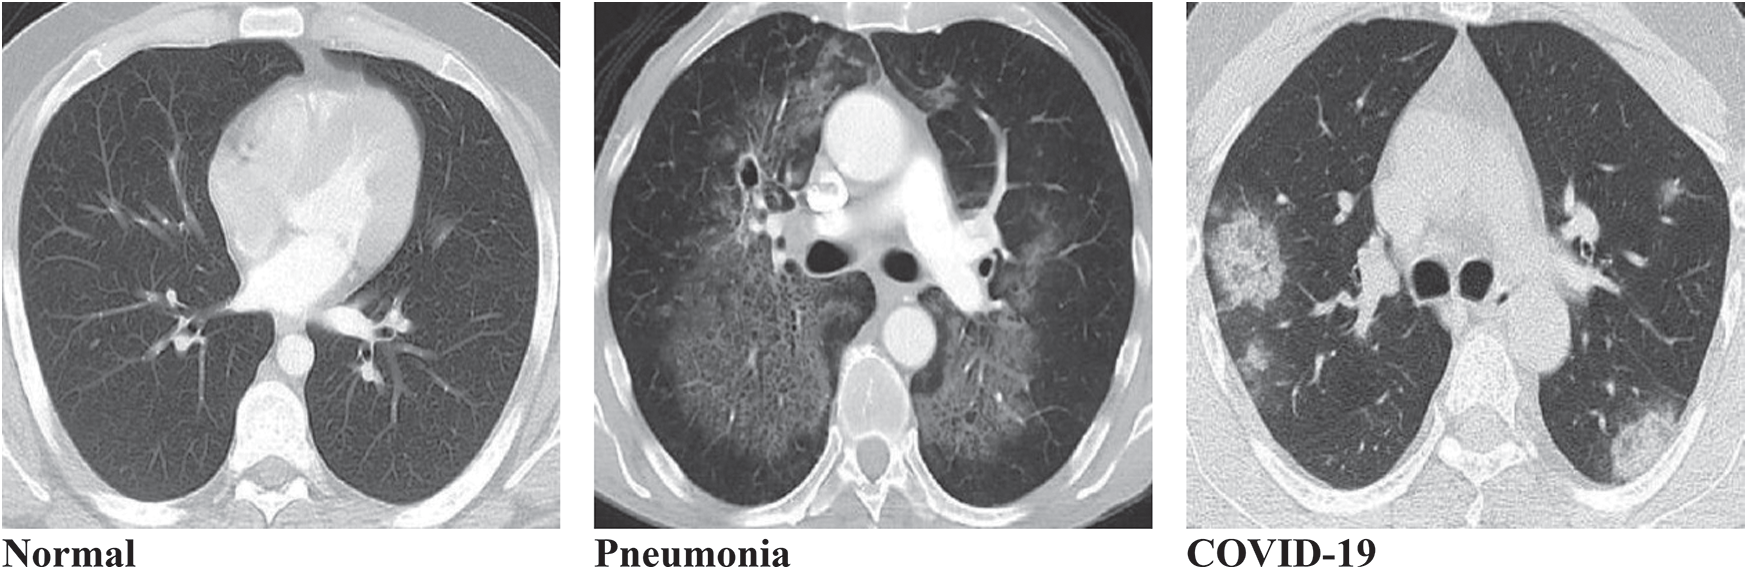

아래 사진을보면 정상인, 폐렴, COVID-19 의 폐 CT 사진입니다.

아래 사진을 기반으로 하면 다음과 같이 해부학적으로 병변을 분류할 수 있겠죠.

- Normal: 깨끗함

- Pneumonia: 광범위하게 GGO(Ground Glass Opacity)가 퍼져있음

- COVID-19: peripheral부분에 GGO가 위치하기도 하며, 진행단계에 따라 GGO 정도가 심해지는 consolidation 현상도 볼 수 있습니다.

※ 물론 이것은 아래 사진만 살펴본 예입니다. 실제로 폐렴(pneumonia)은 그 종류가 다양하기 때문에, CT 상에서 보여지는 특징도 굉장히 다양합니다.